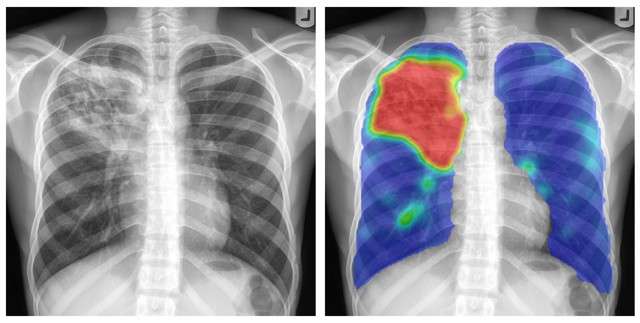

Ho studiato fisica e ho completato un dottorato di ricerca in analisi della diagnostica per immagini nel 1996, sviluppando programmi per computer che analizzano le radiografie del torace sfruttando l’intelligenza artificiale (IA). Alla fine degli anni ’90 volevamo mettere i radiografi digitali del torace con software di IA in Paesi dove la tubercolosi era molto diffusa, perché permette uno screening più veloce e più ampio, senza la necessità di sviluppare immagini su pellicola. Tuttavia, le apparecchiature di radiografia erano troppo costose all’epoca.

Nel 2012, il ‘deep learning’ (apprendimento profondo) ha preso piede, rendendo più popolare l’utilizzo di IA nella diagnostica per immagini. Mi sono trasferito per lavorare in un’università nei Paesi Bassi orientali, e lì ho creato un gruppo di 70 ricercatori per l’analisi della diagnostica per immagini. Cinque anni fa abbiamo iniziato a lavorare con i reparti di patologia per digitalizzare le immagini. Il problema è che, se conservate per uso medico, queste immagini molto grandi occupano tantissimo spazio. Pertanto, i reparti sono costretti in qualche modo a cancellare tutte le immagini dopo tre mesi, impedendoci di usarle per il deep learning. Ora che progressivamente i sistemi di archiviazione stanno diventando più economicamente accessibili, stiamo per risolvere questo problema. Sono certo che entro 10 anni a questa parte tutti i reparti di patologia saranno digitalizzati.

In Svezia è stato condotto uno studio di simulazione in cui è stato usato il più recente sistema IA di mammografia. I ricercatori lo hanno paragonato ai metodi di cura tradizionali. Hanno scoperto che il sistema di intelligenza artificiale funzionava come i radiologi dell’ospedale superando addirittura le prestazioni di alcuni. Così, hanno proposto di permettere che una grande percentuale di mammografie venisse letta solo dal sistema di IA. Se il sistema rilevava un problema, lo avrebbe notificato in modo che un radiologo potesse investigarlo.

La simulazione ha dimostrato che questo procedimento funziona. Tuttavia, non è stato implementato. Fu sostenuto invece che l’ospedale avrebbe dovuto fare una sperimentazione prospettica. Una sperimentazione può costare facilmente intorno ai 10 milioni di euro, per cui avevano bisogno di trovare ingenti finanziamenti. La sperimentazione avrebbe richiesto anni. Sono sicuro che quando avranno completato la prova, il software di IA avrà fatto così tanti progressi che questa tecnologia convalidata prospetticamente sarà già obsoleta.

Questa è la sfida che dobbiamo affrontare: dobbiamo convalidare i sistemi prima che possano essere utilizzati, ma ciò richiede tempo a causa delle normative, e nel frattempo questi sistemi stanno rapidamente migliorando.